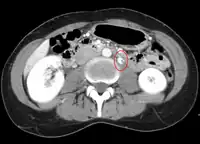

Thrombosis in the left renal vein associated with dilation- Summary video explaining signs and symptoms as well as etiology of nutcracker syndrome